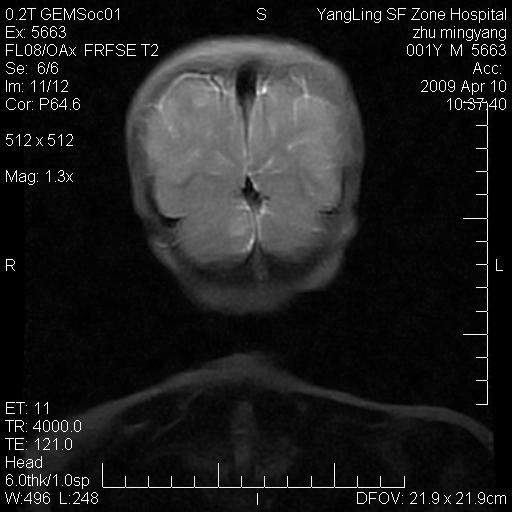

患者:1岁半,两天前外伤收住我院,ct检查小脑占位

考虑星形细胞瘤,建议增强

髓母细胞瘤或血管母细胞瘤,增强后可以鉴别;影像资料见 <。鱼博浪老师的《中枢神经系统ct与mr鉴别诊断》 小脑部肿瘤章节。

髓母细胞瘤或血管母细胞瘤!支持!

支持考虑髓母细胞瘤

考虑----髓母细胞瘤可能性大

考虑髓母细胞瘤或室管膜瘤。

支持髓母细胞瘤。

考虑髓母细胞瘤。

考虑髓母细胞瘤或星形细胞瘤

考虑髓母细胞瘤.

小脑肿瘤.考虑髓母细胞瘤可能.

就病灶部位及临床资料首先考虑髓母.